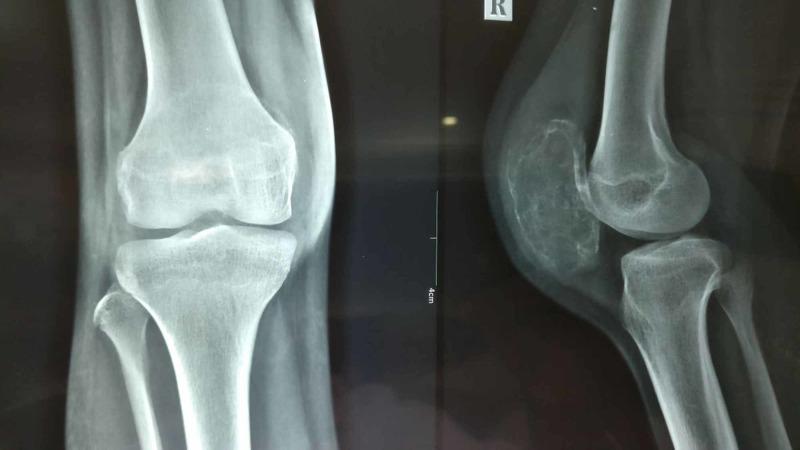

A 15-year-old girl presented with pain and swelling on the anterior aspect of the right knee for one year. The radiological evaluation with x-rays and magnetic resonance imaging suggested a benign aggressive lesion of the right patella with a cortical breach. Core needle biopsy of the lesion revealed it to be a giant cell tumor (GCT). She was treated with total patellectomy and end-to-end repair of quadriceps to the patellar tendon. The histopathological report of the whole specimen revealed it to be a GCT with secondary aneurysmal bone cyst (ABC). After 24 months, she was asymptomatic, and there was no evidence of local recurrence or distal metastasis. An extensive review of the literature revealed only four cases of combined GCT with secondary ABC in the patella. Though rare, GCT with secondary ABC of the patella should be kept as a differential diagnosis for anterior knee pain and swelling in young patients. The diagnosis is solely based on histopathological findings. It is imperative to obtain a precise tissue diagnosis in the preoperative period to plan appropriate treatment.

一名15岁女孩因右膝前部疼痛和肿胀就诊,症状已持续一年。X线和磁共振成像的影像学评估显示右髌骨有一个良性侵袭性病变,伴有皮质破坏。对该病变进行的粗针穿刺活检显示为骨巨细胞瘤(GCT)。她接受了全髌骨切除术,并将股四头肌与髌腱进行端端修复。整个标本的组织病理学报告显示为伴有继发性动脉瘤样骨囊肿(ABC)的骨巨细胞瘤。24个月后,她没有症状,也没有局部复发或远处转移的迹象。广泛的文献回顾显示,仅有4例髌骨合并继发性ABC的骨巨细胞瘤病例。虽然罕见,但髌骨继发性ABC的骨巨细胞瘤应作为年轻患者膝前疼痛和肿胀的鉴别诊断之一。诊断完全基于组织病理学检查结果。术前获得精确的组织诊断以规划适当的治疗至关重要。